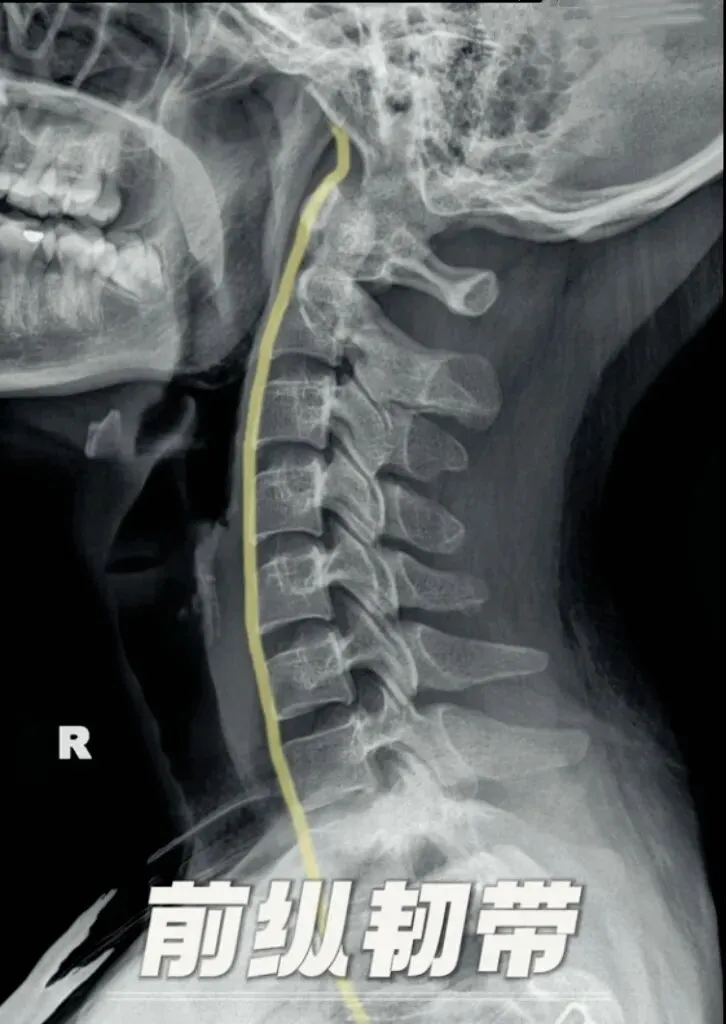

其次是前纵韧带,是椎体前面延伸的一束坚固的纤维束,上自枕骨大孔前缘下达第一或第二骶椎椎体,主要防止脊柱过度后伸和椎间盘向前突出的作用。

颈椎前纵韧带钙化多发生于颈4到6节段,

需要鉴别的类似影像有,颈椎椎体前缘骨折,骨折断茬明显且边缘较锐利,有明确外伤;

还有强直性脊柱炎,呈竹节状改变;

弥漫性特发性骨肥厚,至少连续四个相邻椎体前外侧缘出现流柱状钙化或骨化。

椎间小骨与前纵韧带钙化较难鉴别,所以容易被误认为前纵韧带钙化。